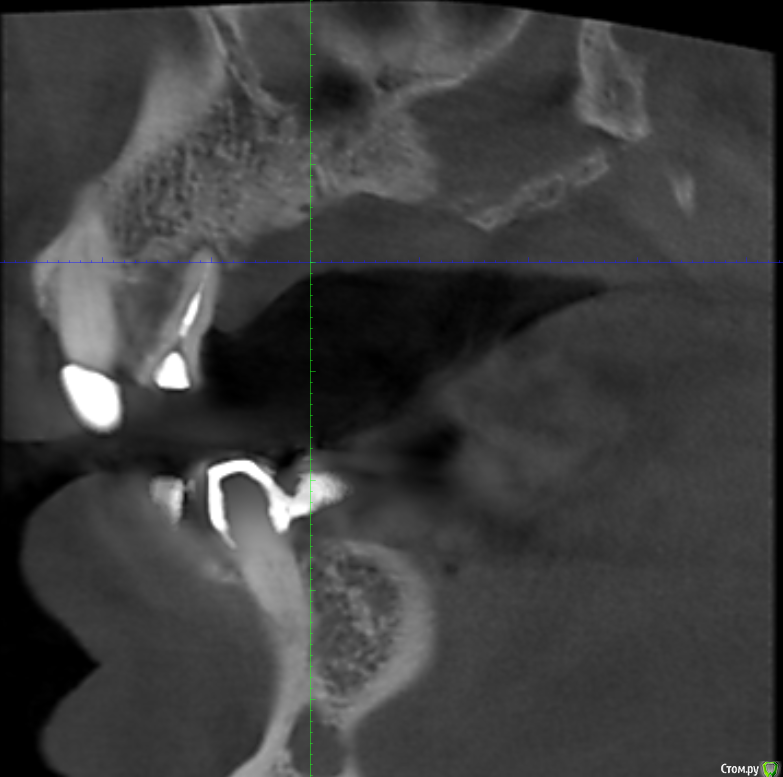

Serg2018 Опубликовано 28 ноября, 2018 Автор Поделиться Опубликовано 28 ноября, 2018 Вот пытаюсь выложить несколько срезов КТ правой стороны, надеюсь, я это правильно понял, делаю впервые. Также тыкал мышкой и она мне что-то замеряла, если в мм, то получается, что в самой тонкой части толщина 2,8 мм? или это я все неправильно понимаю? Ссылка на комментарий

Nazim_NV86 Опубликовано 28 ноября, 2018 Поделиться Опубликовано 28 ноября, 2018 (изменено) Sirona Galileos ?Должно быть окно, где срезы видны как распил. Сечение. Лучше на этом измерять. Можете всю томограмму загрузить на яндекс диск и выложить ссылку. Но сначала проверьте как работает запуск. На той программе, что выше написал, запуск скорее всего возможен только с диска. Если среди файлов на диске есть файл DCM, то его одного достаточно. Просмотрщик не нужно выкладывать. Изменено 28 ноября, 2018 пользователем Nazim_NV86 Ссылка на комментарий